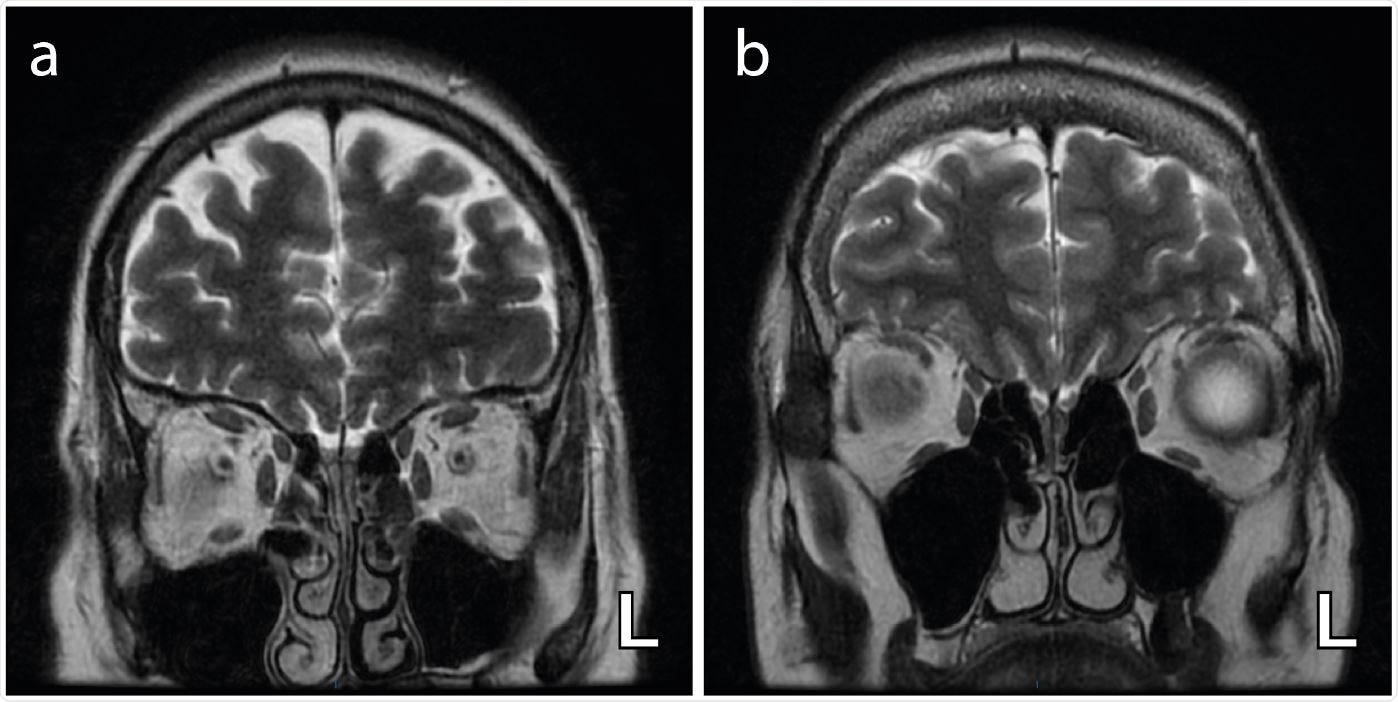

Axial T2-weighted coronal images demonstrating bilateral and complete obliteration of the olfactory clefts (a) with no associated olfactory bulb asymmetry and (b) with asymmetry of the olfactory bulbs (left (L) bulb relatively enlarged) .

The study results showed bilateral blocking of the olfactory cleft in 6 patients and subtle olfactory bulb asymmetry in 3 patients. No abnormalities in the MRI signal downstream of the olfactory tract was noted. Heterogeneous abnormalities (decrease or increase) were observed in glucose metabolism in core olfactory and high-order neocortical areas. The team found a correlation between regional cerebral glucose metabolism and the severity and duration of COVID-19-related loss of smell.